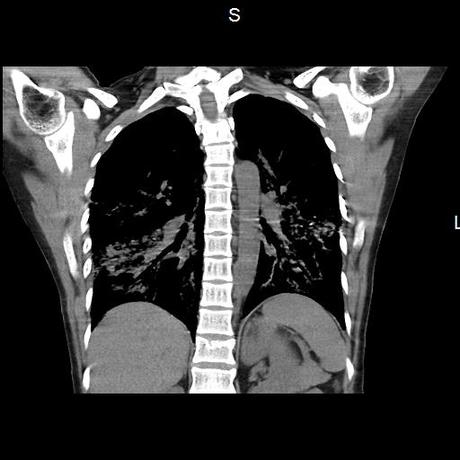

Se realiza volumen de tórax en fase simple, desde los opérculos torácicos hasta los hemidiafragmas, observándose:

El parénquima pulmonar con areas parcheadas difusas en vidrio despulido combinadas con otras areas hipodensas de baja atenuación debidas a atrapamiento aéreo y engrosamiento intersticial y zonas de fibrosis de predominio en lóbulos medios e inferiores de ambos pulmones.

- LOS HALLAZGOS PUEDEN ESTAR EN RELACIÓN A NEUMOPATIA INTERSTICIAL PROBABLE ETIOLOGIA HIPERSENSITIVA VS AUTOINMUNE/BACTERIANA/FUNGICA.